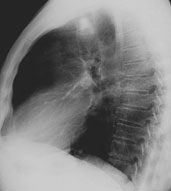

Ein 58-jähriger, sportlich aktiver Mann sucht Sie in der Sprechstunde auf. Er klagt über eine Leistungsminderung und Husten mit etwas weisslichem Auswurf seit ca. 2-3 Wochen. Dazu subfebrile Temperaturerhöhung.

In der Anamnese erfahren Sie, dass der Patient früher geraucht hat (30 packyears), seit 10 Jahren allerdings nicht mehr. Kardiopulmonale Vorerkrankungen werden verneint. Die Lungenauskultation zeigt keine pathologischen Befunde.

Sie beschliessen, ein Thorax-Röntgenbild durchzuführen:

Thorax seitlich

Wie beurteilen Sie das Röntgenbild in Kombination mit der Klinik?